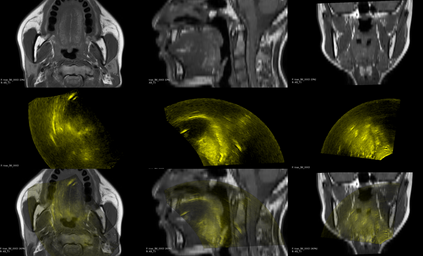

Purpose: Trans-oral robotic surgery (TORS) using the da Vinci surgical robot is a new minimally-invasive surgery method to treat oropharyngeal tumors, but it is a challenging operation. Augmented reality (AR) based on intra-operative ultrasound (US) has the potential to enhance the visualization of the anatomy and cancerous tumors to provide additional tools for decision-making in surgery. Methods: We propose and carry out preliminary evaluations of a US-guided AR system for TORS, with the transducer placed on the neck for a transcervical view. Firstly, we perform a novel MRI-transcervical 3D US registration study. Secondly, we develop a US-robot calibration method with an optical tracker and an AR system to display the anatomy mesh model in the real-time endoscope images inside the surgeon console. Results: Our AR system reaches a mean projection error of 26.81 and 27.85 pixels for the projection from the US to stereo cameras in a water bath experiment. The average target registration error for MRI to 3D US is 8.90 mm for the 3D US transducer and 5.85 mm for freehand 3D US, and the average distance between the vessel centerlines is 2.32 mm. Conclusion: We demonstrate the first proof-of-concept transcervical US-guided AR system for TORS and the feasibility of trans-cervical 3D US-MRI registration. Our results show that trans-cervical 3D US is a promising technique for TORS image guidance.